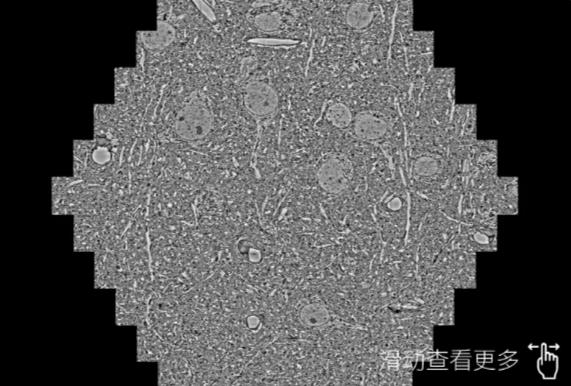

鼠脑切片。左图使用琼中蔡司琼中扫描电镜MultiSEM706对165μmx143pm面积区域成像,耗时仅需1.5秒。右图为鼠脑切片中30μm区域放大效果。样品由芝加哥大学B.Kasthuri提供。

使用蔡司高速琼中扫描电镜MultiSEM对1mm²人脑皮层组织进行高分辨成像,并对其中的各种细胞结构进行三维重构分析。左图展示了2x3mm²组织平面中锥体神经元的三维重构效果。右图显示了局部体积神经元三维重构。图像由哈佛大学chtman实验室提供,渲染图由D. Berger 制作。